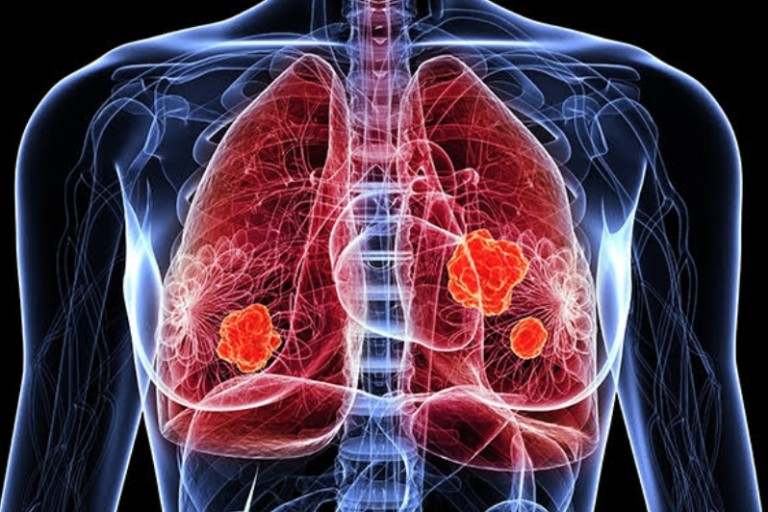

폐암은 초기 자각 증상이 뚜렷하지 않아 굉장히 진행된 상태에서 발견되는게 대부분입니다.. 그렇지만 조기 폐암은 매우 작은 부분만 절제해도 치료가 가능하며 생존율이 70~90%에 이른다.

폐암 증상에는 기침, 체중 감소 흉통, 혈담 즉 피가 섞인 가래, 호흡곤란 등이 있지만, 위 증상은 다른 폐 질환에서도 나타날 수 있는 증상으로 구분하기가 어렵다. 그리고 폐암 초기에는 특별한 증상이 없는 경우가 대부분이라서 최근 흡연뿐 아니라 미세먼지 등 여러가지 요인으로 폐암이 발생하는 경우가 많아 정기검진으로 조기에 발견하는 것이 중요며 폐암 검진을 위해서는 특히나 저선량 흉부 CT를 촬영하는 것이 좋다라고 전문가들은 말하고 있습니다..